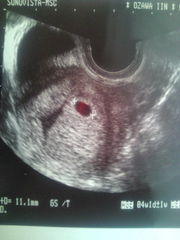

以下、妊娠発覚にあたって、エコー写真など。

◆ 妊娠発覚にあたって ◆

1週間後(5W)

無事赤ちゃんの袋を確認!!!

さらに1週間後(6W)

さらに、1週間後(7W)

心拍を無事確認。

しかし、赤で囲んだ部分が出血しているとのことで

なるべく安静にとのこと。

その後(9W)

出血がだいぶ治まっていて良好とのこと。

赤ちゃんもちゃんと成長しているようで

ようやく一安心。